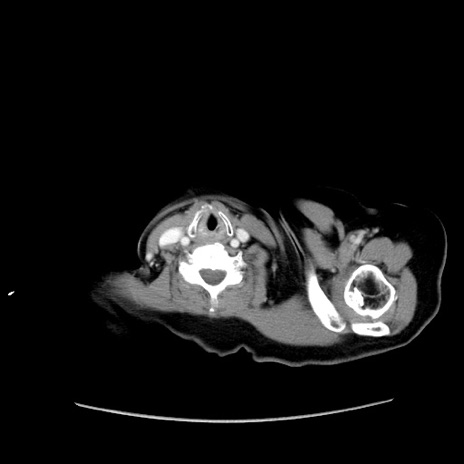

冠状断像